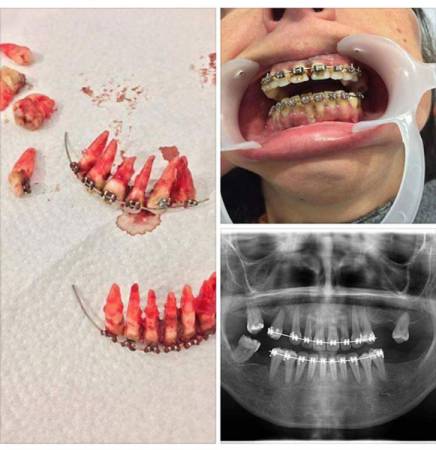

自己亂綁牙 後果好嚴重

菲律賓牙醫Eduardo O. Ricio日前分享一張照片,提醒廣大愛美人士,趕時髦整牙可能產生的可怕後果,就是像照片中的一樣,整板牙隨著牙套全部脫落。這則帖子在網上引發強烈關注,短短17小時內,分享次數就超過2.2萬次。

眾多醫學及生物學專家也紛紛留言加以說明,照片中的情況並非聳人聽聞,因為牙醫整牙時,力度至關重要,如果力度過大,就可能導致骨骼碎裂,以致牙齒鬆動,隨後牙齒會因供血不足而死,直至脫落。